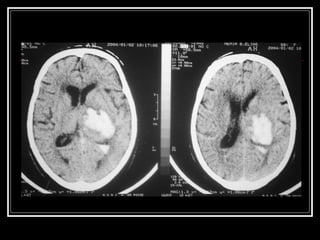

Diagnóstico TC de crânio sem contraste na fase aguda do evento  Limitações: Infratentorial tronco Outros: Lobar? Idade < 45 anos?Hemoventrículo solitário?Sem HAS? RNM e suas variações, arteriografia, etc. para investigação da etiologia do sangramento HDA e HPP (trauma? Anticoagulação? Drogas? Dça hematológica)

Diagnóstico TC decrânio sem contraste na fase aguda do evento Limitações: Infratentorial tronco Outros: Lobar? Idade < 45 anos?Hemoventrículo solitário?Sem HAS? RNM e suas variações, arteriografia, etc. para investigação da etiologia do sangramento HDA e HPP (trauma? Anticoagulação? Drogas? Dça hematológica)